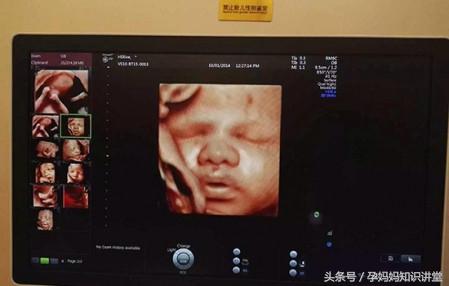

四维彩超提供了包括腹部、血管、小器官、产科、妇科、胎儿彩超图泌尿科、新生儿和儿科等多领域的多方面的应用。其结果是:能够显示您未出生的宝宝的实时动态活动图像,或者其它人体内脏器官的实时活动图像。